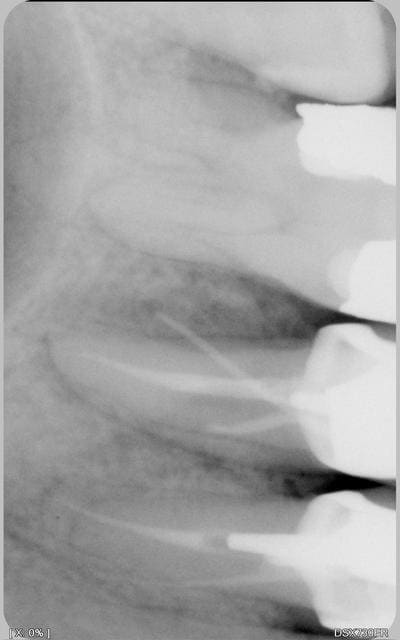

couronne posée il y a 1.5 ans. pas de pb particulier au niveau de douleur a la percussion,mobilité... pas de gonflement,mais une fistule s'est formée en vest de la 25(le cone de la radio qui va sur le coté) que faire? ab, 48 heures après la fin, rebelotte. curetage peri appical? caa marché 8 jours. et pourtant le patient n'a pas mal, juste ce bouton a la con qui est apparu qd la couronne s'est décollée.le ttmt a été refait avant la pose

la radio

Je ne suis qu'une AD mais petite idée : la dent ne s'est pas fracturée dans l'axe du cône? C'est peut être ce qui a provoqué le descellement de la couronne, surtout que le pivot à l'air aussi dans l'axe du cône.

Tu es sûr que c'est une fistule et pas un problème dermato ? Ton cône, si il est bien placé, semble pointer sur le néant. Sur quelle longueur approximative s'enfonce-t'il ?

le sondage paro ne donne rien pas de perte d'attache. pas de sensations de fêlures au toucher.pas de douleur en acrasant. couronne non mobile et dent idem.le decollement du lambeau a montré une cavité beante entre 25 26

1°) Le canal que tu a traité me semble un peu court niveau obturation. As-tu réalisé ta LT avec un localisateur d'apex ?

2°) Tu as presque fait une perforation...

3°) Tu as un deuxième canal non traité.

Je m'explique sur ce dernier point :

Ton obturation n'est pas centrée par rapport aux limites externes de ta racine --> donc il y a un deuxième canal.

Celui que l'on voit (traité à 1/2), me semble trop excentré pour être le "vrai" deuxième canal.

NB : il se peut aussi que tu sois face à un seul canal en 8 et que tu n'ais obturé qu'une partie.

le pepin est au niveau du 1/3 moyen. la couronne n'est pas plus débordante que celle des copains.

ce que j'ai vu en decollant la gencive est qu'il y a une cavité beante en 5 et6.

Je crains le pire: 2 canaux vestibulaires, comme le laisse supposer l'orientation du tiers coronaire du canal partiellement obturé, de même que sur la 4...

Cette variation anatomique est possible.

Il serait judicieux de varier les incidences sur d'autres clichés, voire même de comparer avec les homologues si par chance elle ne comportaient pas de traitement canalaire, afin de "détacher" les canxu MV et DV sur l'image en incidences distale puis mésiale, voire individualiser les apex en incidence semi-occlusale? (pardon pour la terminologie à peu-près-iste)